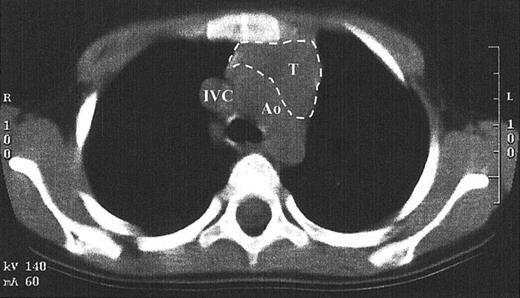

While TRECs are an excellent surrogate marker for thymic function, little direct data exist that show thymopoiesis. This is in part due to the inappropriateness of performing a thymic biopsy in children who have developed normal function. Since the pretransplantation SCID thymus is vestigial, weighing less than a gram, it is difficult to find by radiography.1,14 A computed tomography scan of the anterior mediastinum of the Jak3-deficient SCID patient at 4 years after transplantation shown in Figure 6demonstrates a thymus with a transverse dimension of 3.8 cm, which is normal for age.16 The thymus expansion seen here provides further evidence for thymopoiesis after hematopoietic stem cell transplantation in SCID.

Fig. 6.

Computed tomography scan of the anterior mediastinum of a Jak3-deficient SCID patient 4 years after transplantation.

Thymic tissue is indicated by the dashed lines. It is in the normal position and measures 3.8 cm in its greatest transverse dimension, which is normal for age. Ao indicates aortic arch; IVC, inferior vena cava; T, thymus.